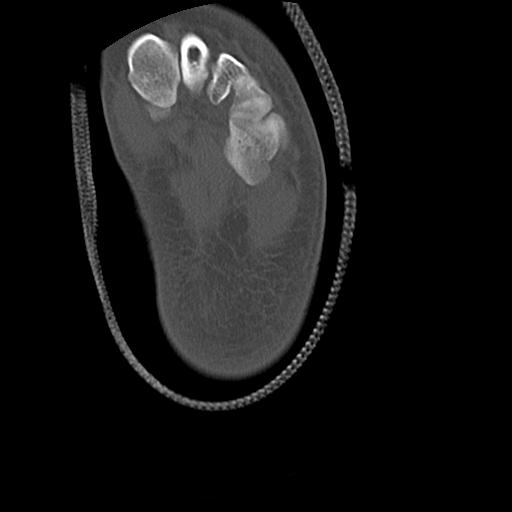

102755 1/4 2R 1/15 2R 右足関節 68歳女性 右三果脱臼骨折